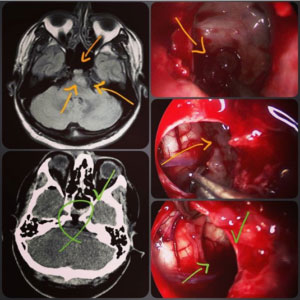

تشخیص کوردوما

پزشک شما را معاینه می کند و ممکن است برای بررسی سلامت عمومی خود آزمایش خون بدهید.سایر آزمایشات ممکن است شامل سی تی اسکن و یا MRI باشد.درمان شما بستگی به این دارد که کوردوما کجا و چقدر بزرگ است.مهم است که کوردوما در اسرع وقت درمان شود.این به کاهش احتمال بازگشت آن (عود) کمک می کند.ممکن است برای برداشتن تومور عمل کنید.پس از آن ممکن است رادیوتراپی انجام دهید.